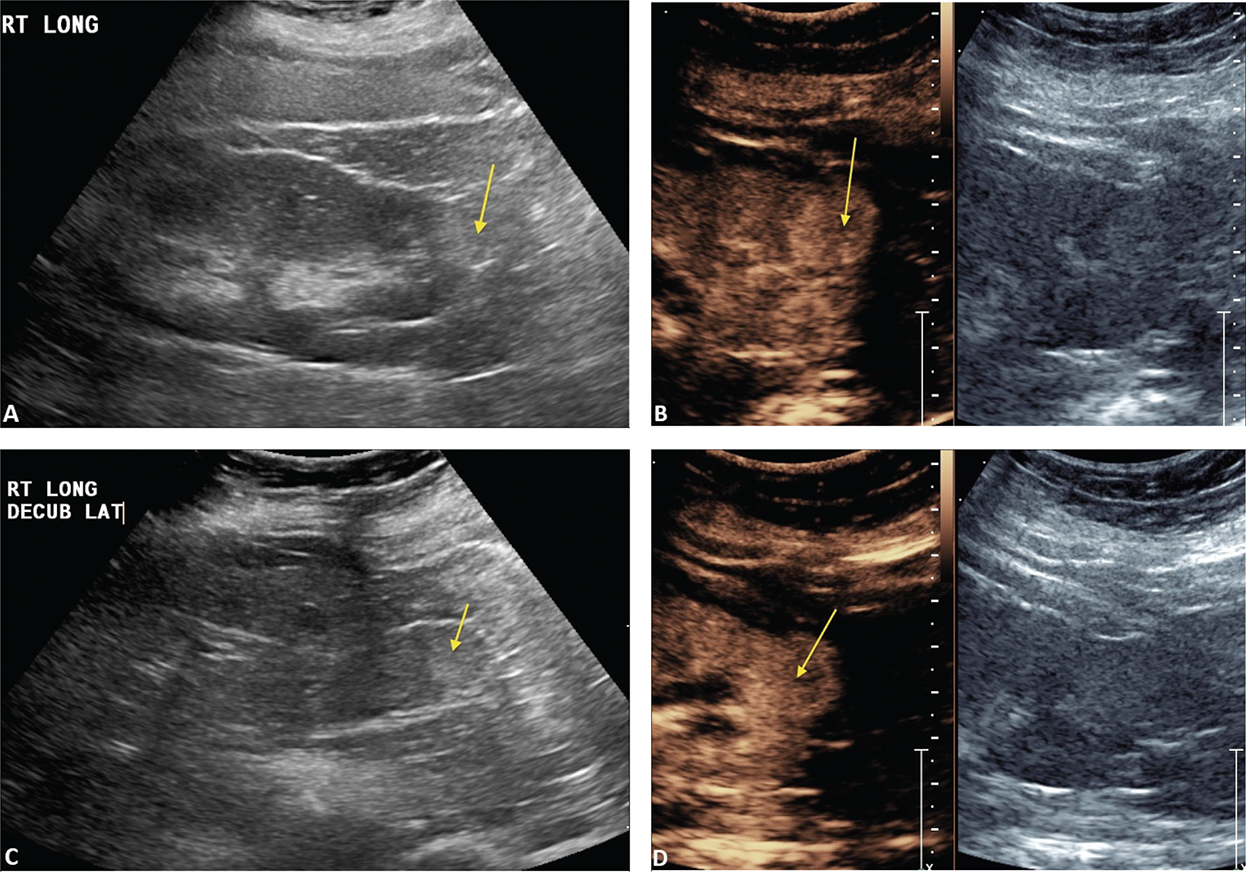

Figure 1 demonstrates the steps in performing a CEUS RFA. Figure 1A is the unenhanced B-mode US before the procedure. In this case, the mass is easily identified. If the mass is not visualized well, a CEUS can be performed to confirm the size and location of the mass. Figure 1B shows the position of the RFA needle in the mass. Figure 1C is the image after the injection of the ultrasound contrast confirming the position of the needle in the mass. Figure 1D shows that there is no flow remaining in the renal mass, confirming complete ablation of the lesion.

Figure 1. Images demonstrating RFA of an RCC. (A) B-mode image of the RCC (calipers) pre-procedure, (B) B-mode image demonstrating positioning of the RFA needle (arrow) in the RCC, (C) image after injection of ultrasound contrast confirming the needle (arrow on low MI B-mode image on right) within the tumor, and (D) CEUS post-procedure demonstrating complete ablation of the RCC (arrow, right).

Figure 2 demonstrates that after the first ablation, a second dose of ultrasound contrast can be performed to evaluate for residual tumor. The CEUS contrast lasts for about 5 min. During the RFA, gas bubbles are generated and appear as CEUS contrast when imaging. Waiting for about 5 min after the completion of the ablation will eliminate this problem. If bubbles still remain in real-time CEUS imaging, the bubbles generated from the procedure will not move whereas the UCA bubbles in residual tumor will be visualized as moving. In this case, a large area of residual tumor (arrows) remains. The CEUS image can be used to reposition the RFA needle into the residual tumor.

Figure 2. Multiple doses of ultrasound contrast can be administered during the RFA procedure. The contrast agents last for about 5 min so that residual enhancement is not present on additional doses. In this case, a CEUS study was performed after the first ablation. Note that there is residual tumor (arrows). The RFA needle can then be repositioned into the residual tumor for additional ablation. This confirms that the tumor is completely ablated at the first setting. The similar process cannot be performed in CT because only one dose of CT contrast can be administered.